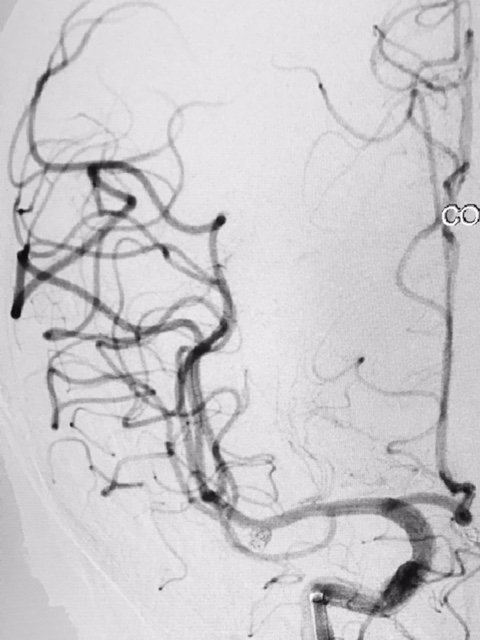

Tratamento de aneurisma cerebral com auxílio de balão duplo lumém e neurostent LEO